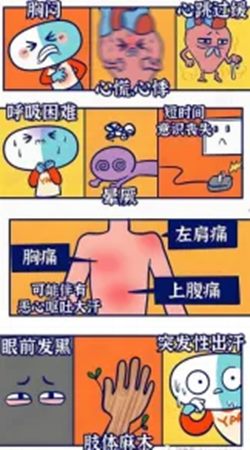

三、猝死前有哪些预警信号?

尽管部分患者毫无征兆突然倒地,但约50% 的人在猝死前数小时至数天会出现“求救信号”:

胸部不适: 压榨性疼痛、闷胀感,可能放射至左肩、左臂或下颌。

呼吸异常: 濒死样喘息(类似鱼出水时的呼吸声)。

神经系统症状: 突发头晕、黑矇、全身抽搐。

自主神经反应: 冷汗淋漓、恶心呕吐、面色苍白。